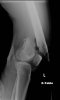

Hope the physio goes well